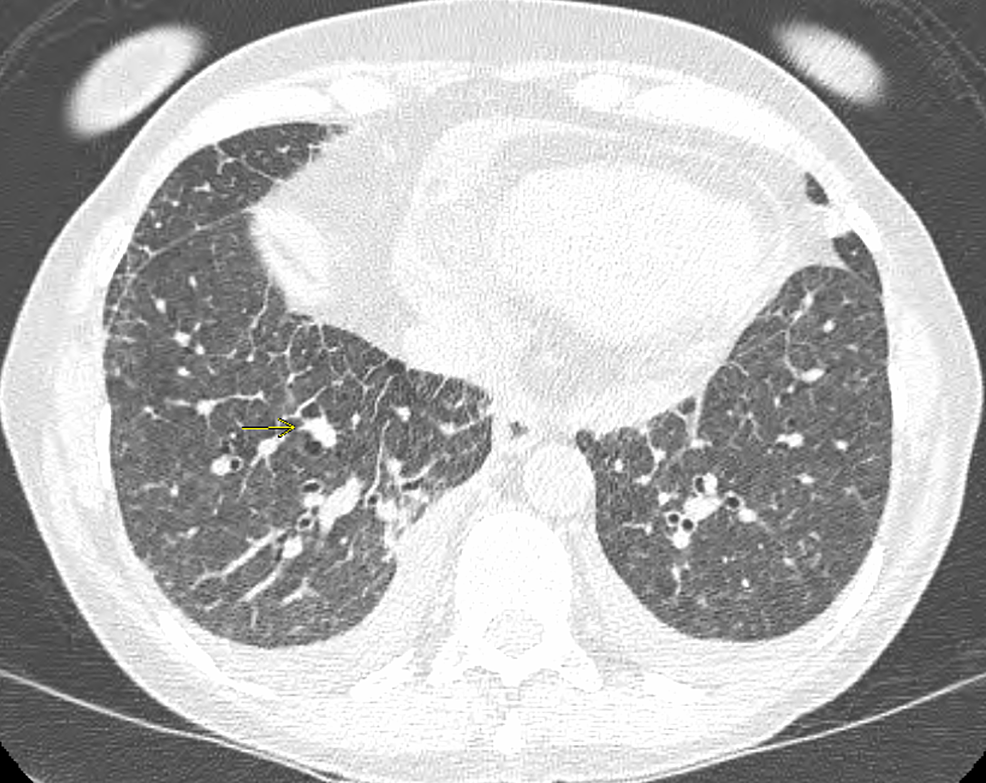

Interstitial Lung Disease or COVID19? A Complex Pulmonary Differential Ild Flare Radiology interstitial lung disease (ild) is a category of diffuse parenchymal lung diseases characterized by inflammation. interstitial lung abnormalities (ilas) are common incidental findings at ct, which progress over 5 years in more than 50% of individuals, and are. Based on the 2016 definition of. interstitial lung diseases may be marked by abrupt flares of disease activity. Ild Flare Radiology.